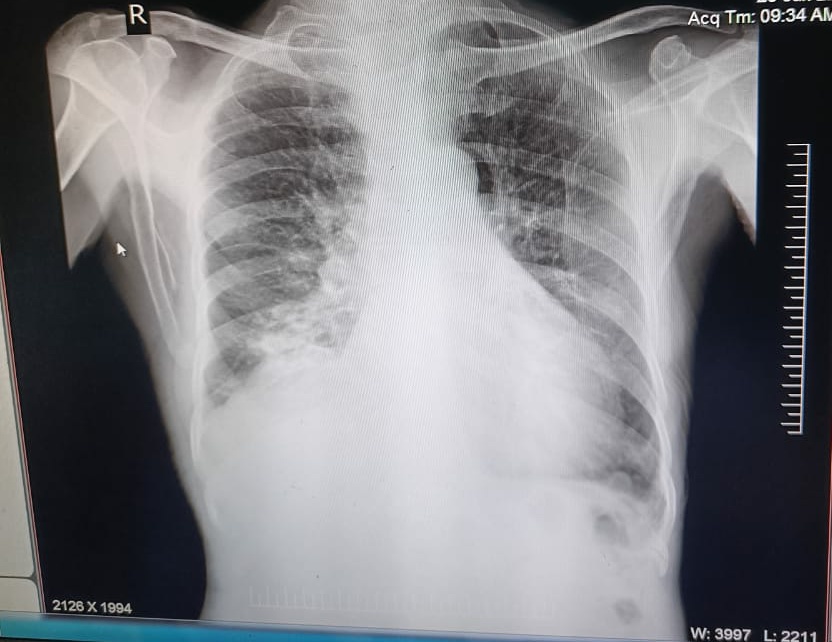

X-ray

Provisional diagnosis: Acute on chronic COPD with Right heart failure( Corpulmonale) with Rt lower lobe pneumonia.